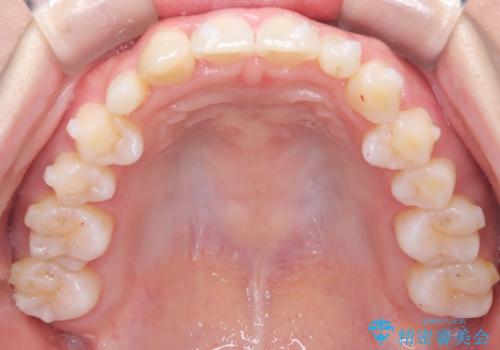

【インビザライン】八重歯が気になる

- 乳歯を抜歯してスペースを確保し八重歯の改善を行いました。

インビザラインをしっかり使用していただいたので、きれいな歯並びになりました。